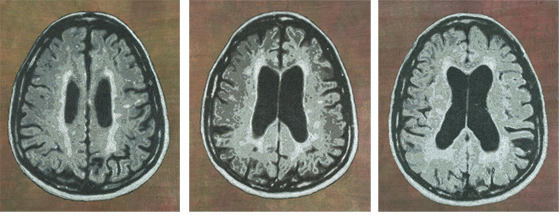

MS Karen 1

MS Karen 2

MS Karen 3